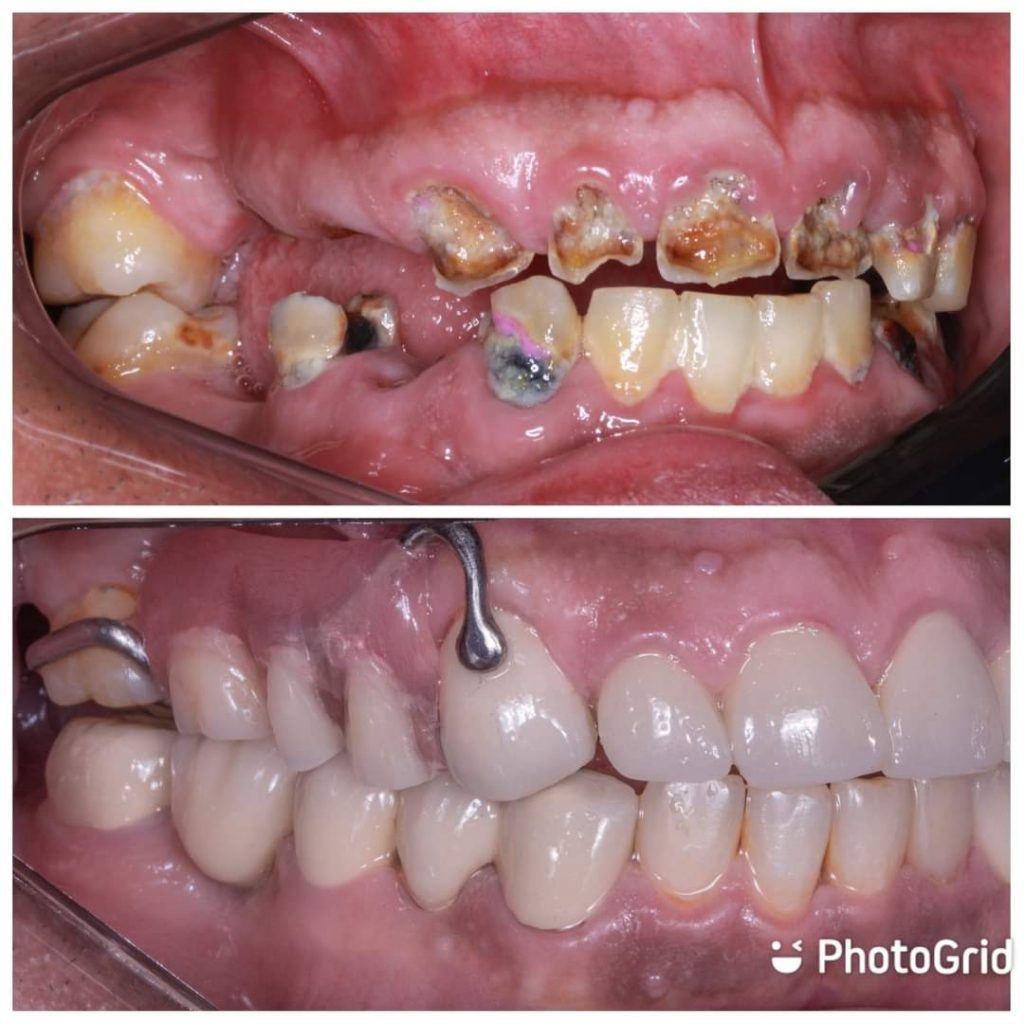

Hi this is my first full mouth rehabilitation case as graduation project .

In this case , I start extra-oral analysis to determine ricketts angle plane for maxillary anterior crowns protrusion to overcome crossbite.

After, proper diagnosis,radiographic and clinical examination , endodontic treatment was done for teeth no 13,12,11..21,22 also, teeth no 33, 34,36

Then, fiber posts and composite cores were performed to badly destructed teeth

PFM bridge on 43,45,47

Tooth 45 used as extra-coronal pier abutment in long span PFM bridge (stress breaking action )